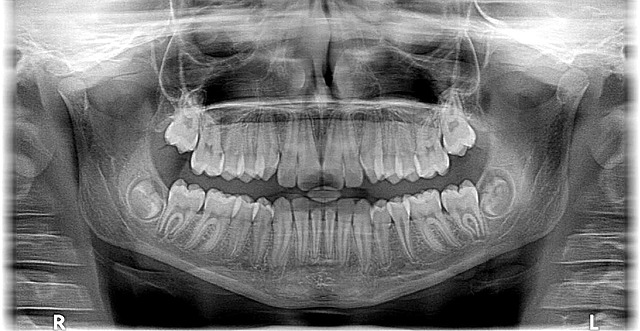

사랑니는 어금니 뒤쪽에 나는 세 번째 어금니로, 보통 10대 후반~20대 초반에 나기 시작합니다. 하지만 사랑니가 정상적으로 나지 않거나, 부분적으로 잇몸에 묻힌 경우에는 여러 문제를 유발할 수 있습니다.

✔ 부분 매복 사랑니: 일부만 잇몸 밖으로 나와 음식물이 끼고 충치 발생 가능

✔ 완전 매복 사랑니: 잇몸 속에 갇혀 염증, 통증, 신경 손상 유발 가능

✔ 옆으로 누운 사랑니: 앞 치아를 밀어 치열이 틀어지고 통증 발생